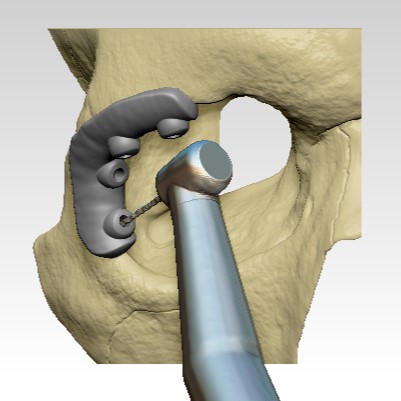

The Master of Science program in Clinical Anaplastology (CA) provides students with knowledge to succeed as clinicians providing facial, ocular (eye), and non-weight bearing somatic (body) prostheses, as well as designing 3D patient-matched models, surgical templates and other 3D printed clinical models.

- Examples of the work created